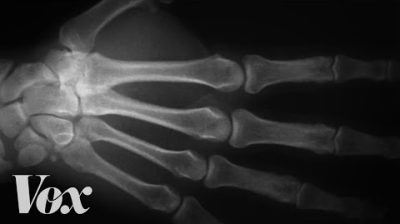

Den ene mannen knakk knokene i den ene hånden i 60 år og ikke den andre. Se videoen for å se hva han fant ut.